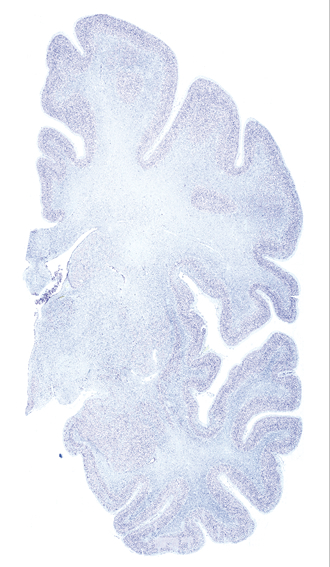

Hi-Resolution Sections · Cells (Nissl Staining) · Virtual Microscopy

Frontal sections (Nissl) from the Atlas Brain: Gallery Slice Single

Microscopy

Slice ID: r3-1195

Plate NR: ca 26

Position: 5,5 mm